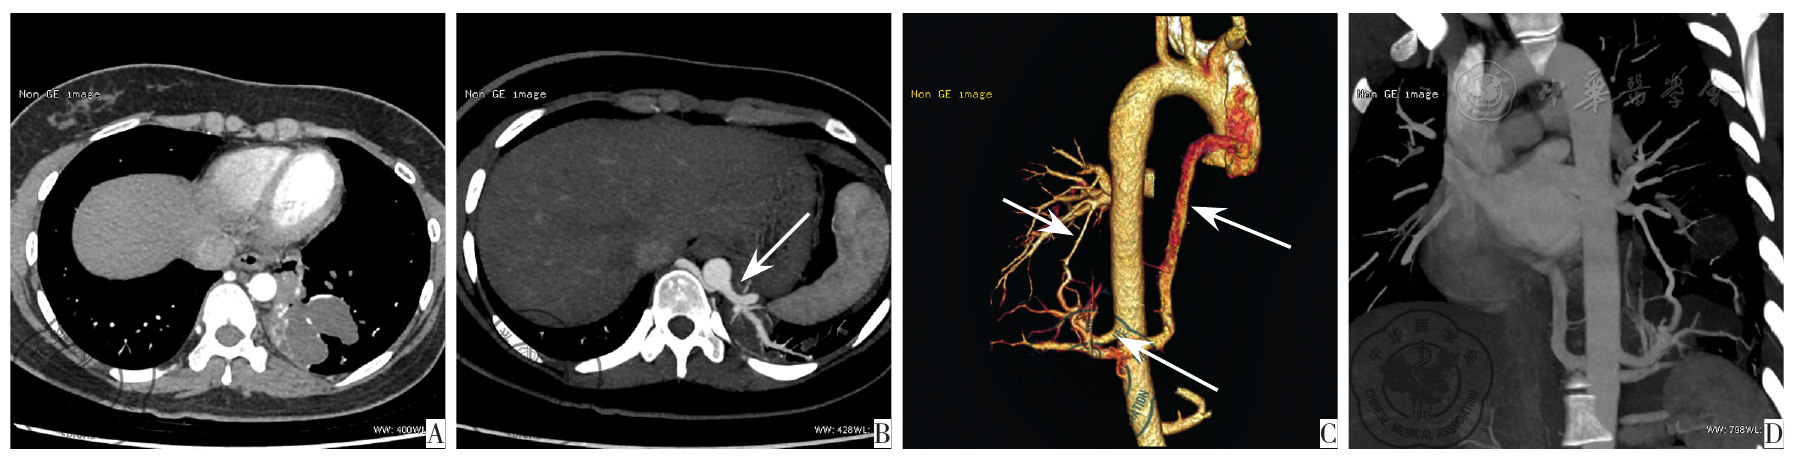

图2 左肺下叶叶内型囊实性肿块型肺隔离症;注:A:CT增强纵隔窗横断位示左下方囊实性肿块、实性部分不均匀强化,囊性部分不强化;B:MIP横断位示供血动脉、引流静脉与肿块关系;C:VR一支粗大供血动脉起自胸主动脉下段(长箭)、引流静脉为左下肺静脉(短箭);D:MIP斜矢状位清晰显示供血动脉的走行、分支形态及与隔离肺组织、左下肺静脉之间的关系